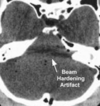

what origin of CT artifact are the following? Beam hardening: Beam becomes "harder" (i.e. its mean energy increases) as it passes through the object because lower energy photons are absorbed more rapidly than high energy photons Produces streaks and dark bands Manufacturer correction: filtration, calibration, special software Operator: tilt gantry, filter selection Partial volume: off-center dense object protrudes into the beam path Use thin acquisition width Photon starvation Undersampling

physics based

what type of artifact is More common in the skull due to thickness of calvarium?

Beam-hardening artifact